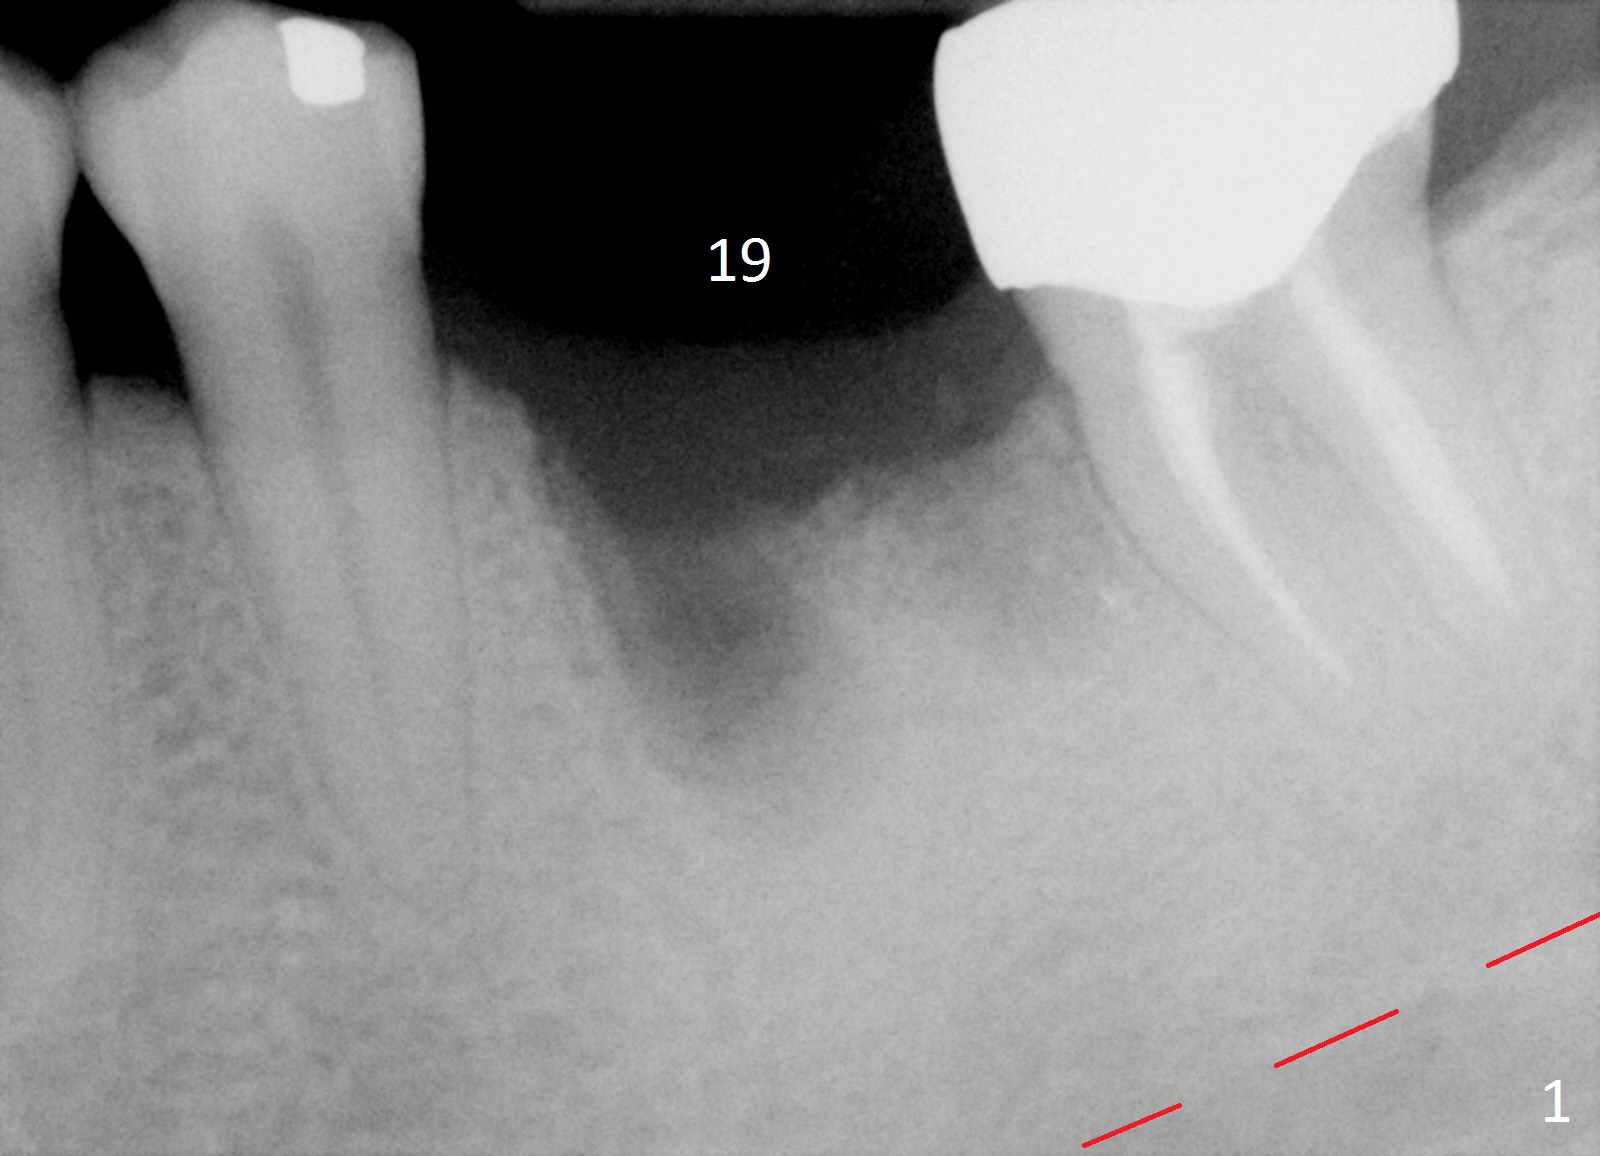

A 42-year-old woman presented to clinic 11 years ago with history of extraction of the tooth #19 two months earlier (Fig.1).  Two months later, a 5x8 mm Bicon implant was placed (Fig.2).  Integrated Abutment Crown was delivered 2 years later (Fig.3) with persistent radiolucency in the mesial socket.  The tooth #18 was extracted with socket preservation 7 years ago.  Recently she returned with chief complaint of chewing pain in the lower left for a while.  The buccal gingiva of #19 is erythematous, edematous and tender (Fig.4).  There are healing abutment at #29 and implant crown at #30.

Periimplantitis at #19 is most likely due to buccodistal placement.  When it is removed (Clindamycin), a smaller IBS or SM implant will be placed immediately and mesiolingually (Fig.3).  For better wound protection with periodontal dressing or provisional, an implant will be placed at #18 at the same appointment.  Draw blood for PRF if the vein is large enough.  Surgical stents have been in cold sterilant.